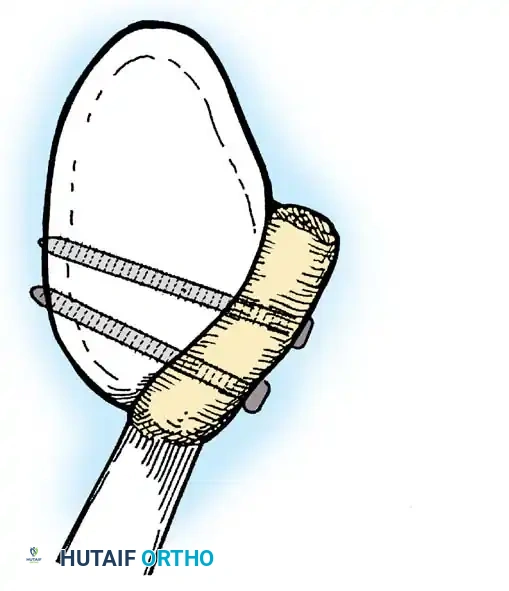

- Anchor Placement: Suture anchors (typically 3 to 4) are placed along the articular margin of the anteroinferior glenoid (from the 5:30 to 3:00 positions for a right shoulder). Anchors must be inserted at a 45-degree angle to the articular surface to maximize pullout strength and avoid joint penetration.

Capsular Shift and Closure

To address capsular redundancy, an inferior capsular shift is performed.

- The arm is positioned in 30 to 45 degrees of abduction and 20 degrees of external rotation.

- The inferior capsular flap is advanced superiorly and laterally, tensioning the IGHL complex. The sutures from the anchors are passed through the shifted capsule and tied.

- The superior flap is then brought down over the inferior flap in a "pants-over-vest" fashion to reinforce the anterior wall and close the rotator interval.

- The subscapularis split is loosely approximated with absorbable sutures. The deltopectoral interval is closed over a suction drain (if necessary), followed by routine subcutaneous and skin closure.